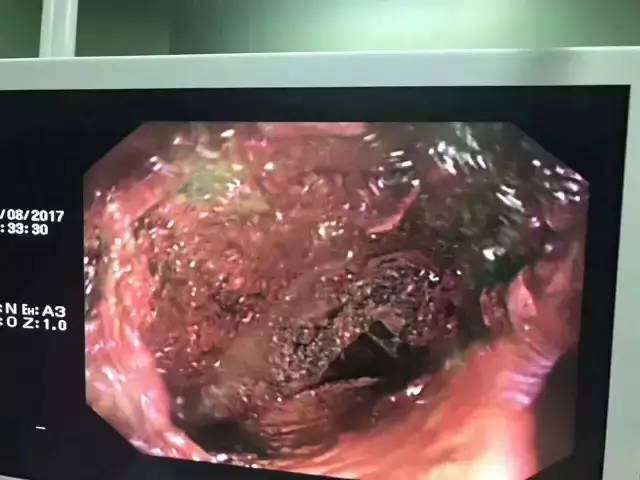

然而,医生在小海的食道中,却发现了一颗纽扣电池!经胃镜探查,纽扣电池周围的食道已经有明显的发黑和糜烂。

(图片来源 微博)